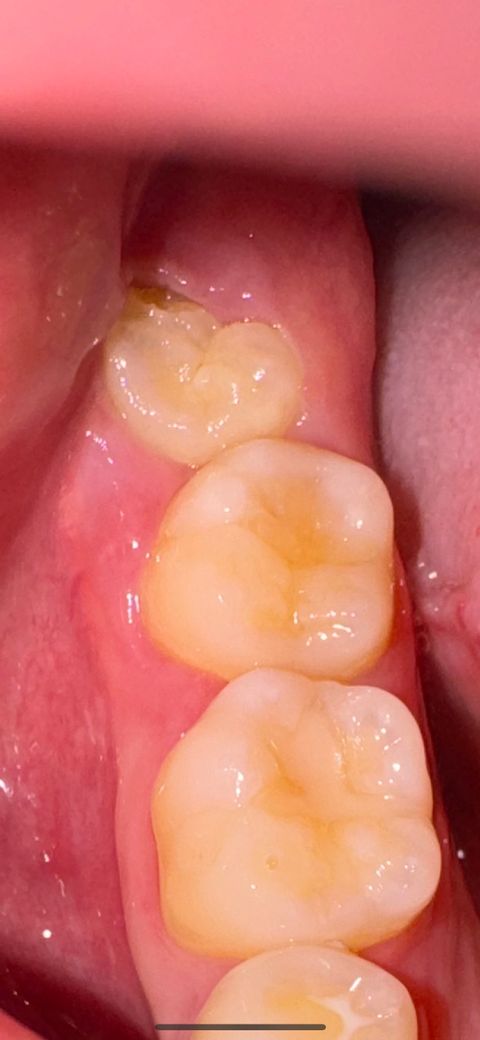

사랑니 옆 어금니 썩은것처럼 보이시나요???

서로 겹치는 옆면에 약간 검은 점이 있는거같기도하고.. 좀 헷갈려서요! 아무런 통증은 없는데…. 사랑니는 겨울에 발치 예정입니다!!! 그때까지 썩지않겠죠?

사랑니 발치는 크게 어려운 케이스는 아닌거 같습니다. 충치도 있어 보이진 않으니 걱정하지 않으셔도 될것같습니다.

현재 사진상으로 충치로 보이지는 않으나 통증이나 불편감이 나타나는 경우에는 바로 치과에 방문하여 상태를 확인해보길 권합니다.

사진으로 봤을 경우에는 특별한 이상이 없어 보입니다. 하지만 인접면의 충치의 경우에는 어떻게 추가적인 검사가 필요할 수 있습니다. 자세한 확인을 위해서 치과에서 진료를 받아보는 것을 권유 드립니다.

사진이 흐리긴 하지만 썩은 것으로 보이진 않습니다. 통증 없으면 급하게 뽑을 필요는 없습니다.

1. 현재 사진상으론 심한 충치는 아닐 것 같습니다

현재 사진에서는 육안으로 보이지 않지만 치아 사이이거나 잇몸 아래에 충치가 생겼을 수도 있습니다. 따라서 현재 충치에 대한 진단을 하기 위해서는 x-ray 등의 촬영이 필요합니다.

임상 사진만으로 봤을 때는 육안 상으로 보일 정도의 큰 충치가 보이지는 않습니다만, 방사선사진을 찍어야만 평가가 가능합니다. 마취 후 발치를 진행하니 너무 걱정하지 않으셔도 됩니다.